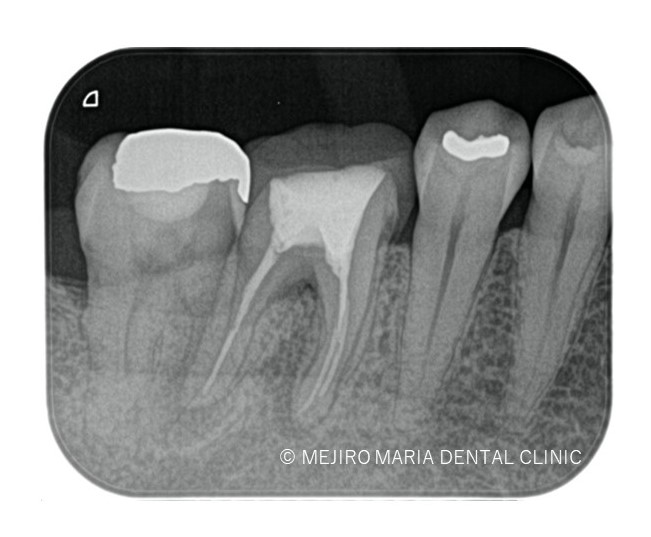

治療はすべて歯科用顕微鏡下(マイクロスコープ)にて行い、前回の治療で充填されている材料をすべて除去した後に破折診査をおこなった。歯科用顕微鏡(マイクロスコープ)下でも遠心根に破折線は見つけられず、通法通り根管治療を終了した。

今回は水酸化カルシウムを貼薬した後、2回目の治療にて根管充填、支台築造処置を終了させている。